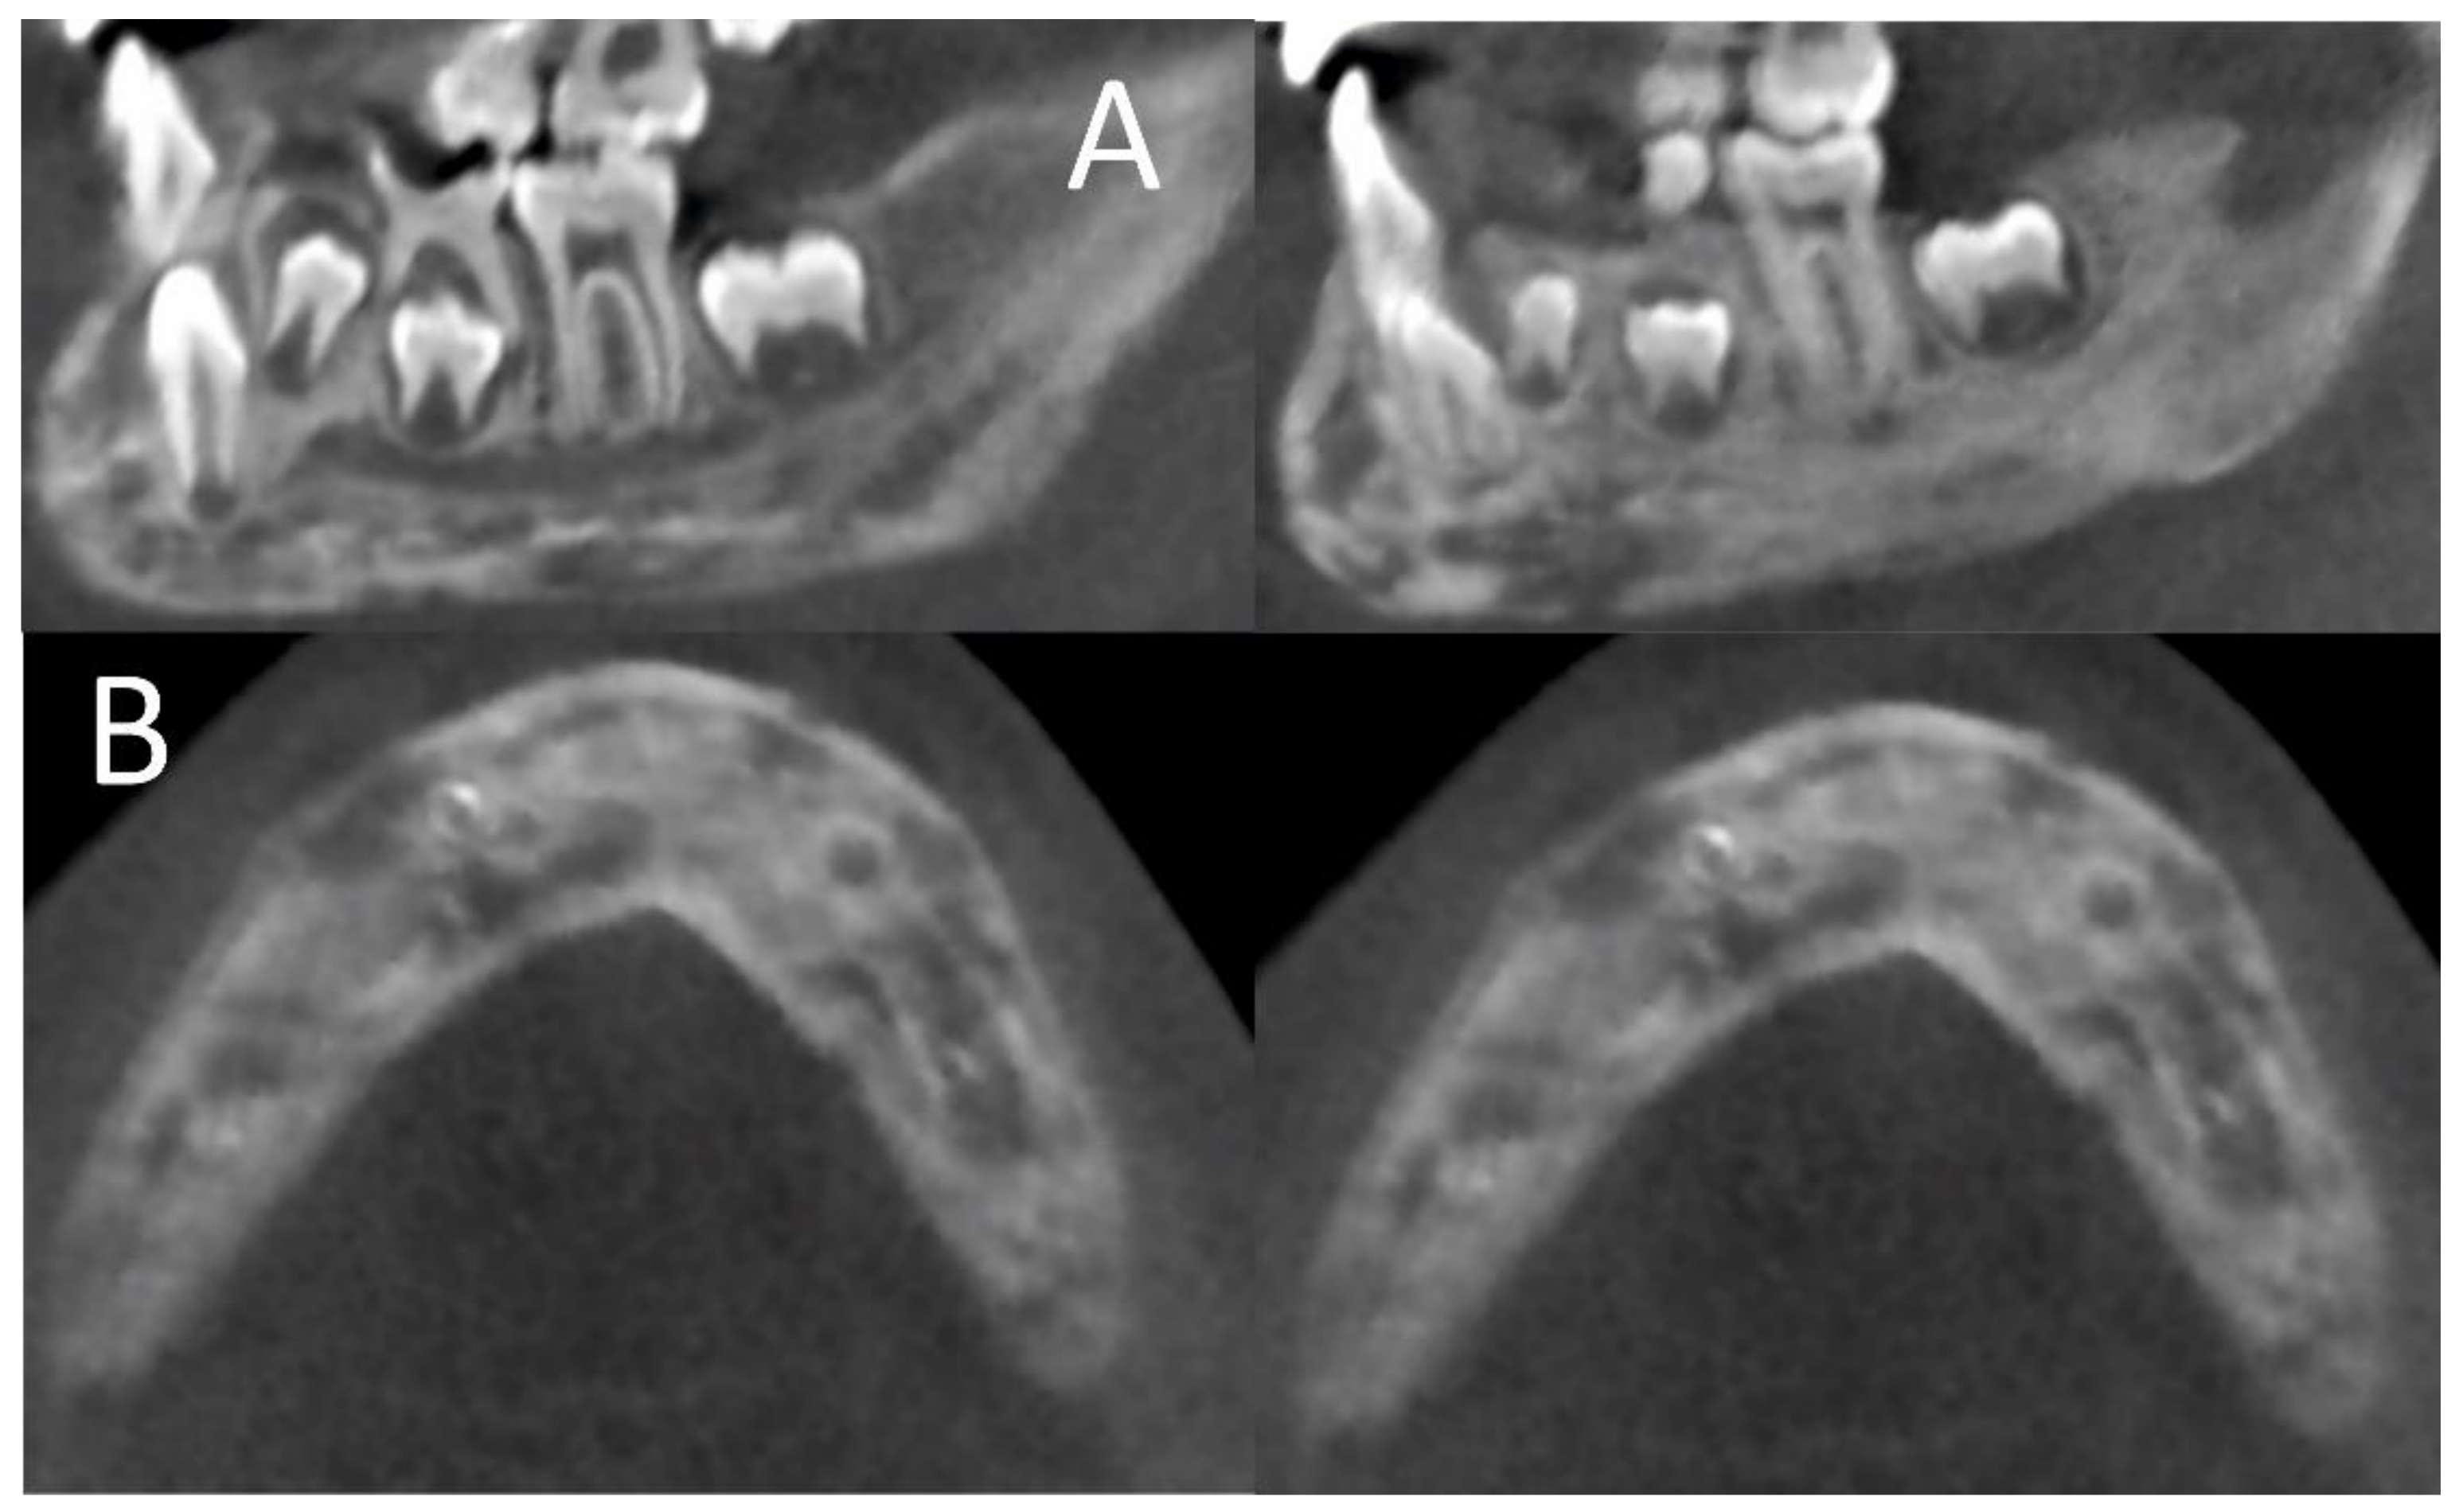

CT of the mandible showing homogenous sclerotic bone of the left Sclerosing Osteomyelitis Mandible    in florid cod, multiple lesions are observed that involve the mandible and/or maxilla bilaterally (figure 1c, d).   it commonly presents within the posterior body or ascending ramus of the mandible and other long bones. 1 it is a form of chronic.  treating chronic diffuse sclerosing osteomyelitis (dso) is challenging and many treatments have been reported.  chronic. Sclerosing Osteomyelitis Mandible.

Diffuse sclerosis of the mandible visible on orthopantomogram and Sclerosing Osteomyelitis Mandible  1 diffuse sclerosing osteomyelitis is a relatively modern term, with earlier literature referring to the condition as sclerosing osteitis, osteosclerosis, enostosis, bone whorls, bone eburnation, hyperostosis, and ossifying osteomyelitis.   in florid cod, multiple lesions are observed that involve the mandible and/or maxilla bilaterally (figure 1c, d).   it commonly presents within the posterior body or ascending ramus of the. Sclerosing Osteomyelitis Mandible.

Figure 2 from Diffuse sclerosing osteomyelitis of the mandible Sclerosing Osteomyelitis Mandible  1 it is a form of chronic.   it commonly presents within the posterior body or ascending ramus of the mandible and other long bones. 1 diffuse sclerosing osteomyelitis is a relatively modern term, with earlier literature referring to the condition as sclerosing osteitis, osteosclerosis, enostosis, bone whorls, bone eburnation, hyperostosis, and ossifying osteomyelitis.  treating chronic diffuse sclerosing osteomyelitis. Sclerosing Osteomyelitis Mandible.